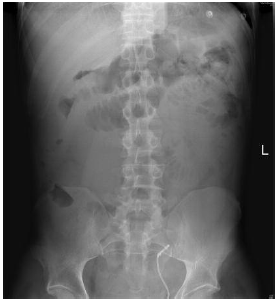

Initially, he was treated with nil by mouth, intravenous fluid, and antimicrobial agents; however, overnight his symptoms worsened with increased pain, abdominal distention, and decreased bowel sounds. An abdominal radiograph showed dilatation of the small bowel, suggestive of an obstruction (Figure 1). An axial computed tomographic scan of the abdomen showed distention of the small bowel with a transition point in the left lower quadrant above the transplanted kidney (Figure 2). The patient underwent an exploratory laparotomy, reduction of the small bowel loop (which was distended but still viable), entrapped through a defect in the peritoneum covering the transplanted kidney (Figure 3). He did not require a bowel resection, and the peritoneal defect was closed with absorbable sutures. His recovery was uneventful.

Figure 1. Abdominal Radiography Showing Dilatation of the Small Bowel